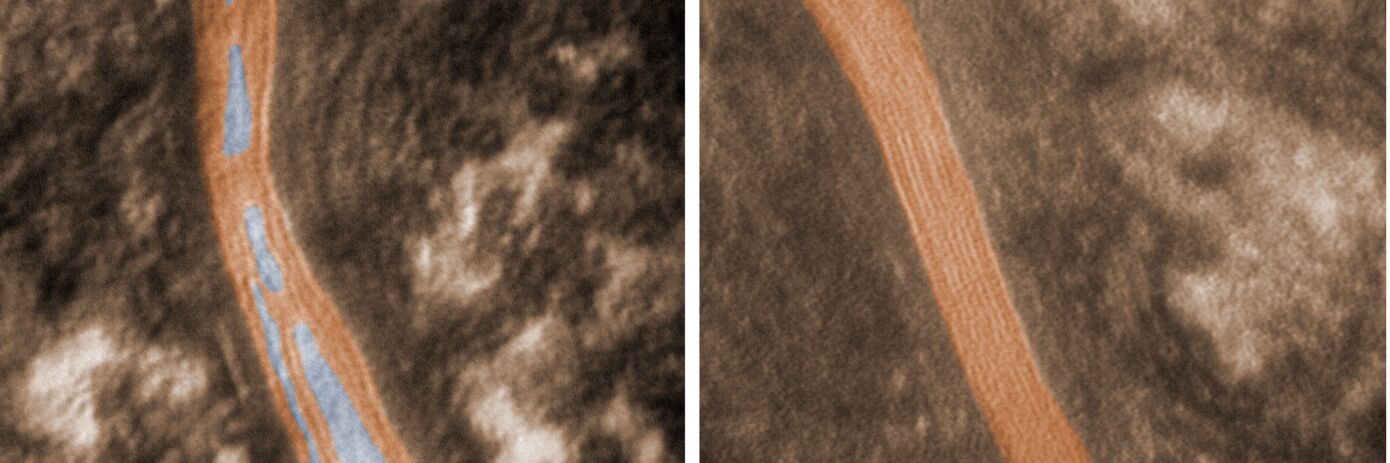

Neben der direkten und sehr präzisen Bestimmung der epidermalen Hautbarriere erhalten Sie eindrucksvolle elektronenmikroskopische Bilder der epidermalen Hautbarriere zum Beispiel vor und nach einer Produktanwendung.

Abb.1: Elektronenmikroskopisches Bild der epidermalen Hautbarriere von Altershaut vor und nach einer Produktanwendung.